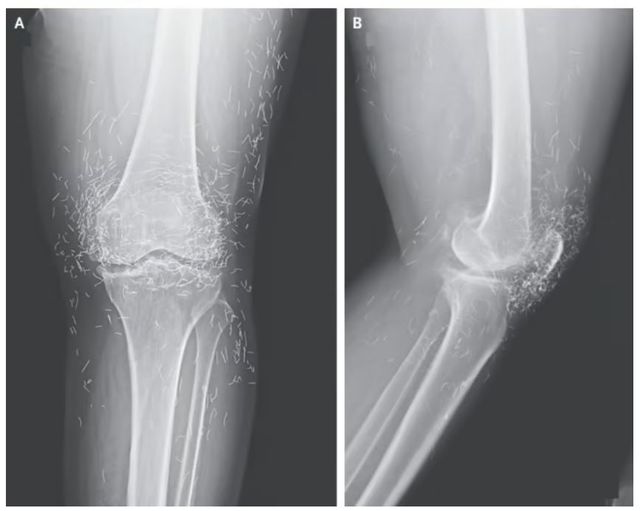

실제로, 2014년 임상 의료 분야의 권위 있는 국제 학술지 《뉴잉글랜드 의학 저널》에도 금침 시술 사례가 보고된 바 있다.

당시 보고된 사례는 퇴행성 관절염을 앓고 있던 65세 한국 여성의 무릎 엑스레이 사진으로, 다량의 금침이 발견됐다. 연구진은 해당 환자가 항염제 치료를 받았으나 효과가 없어 금침 요법을 선택했다고 설명하며, 금침이 방사선 검사를 복잡하게 만들 수 있다고 지적했다.